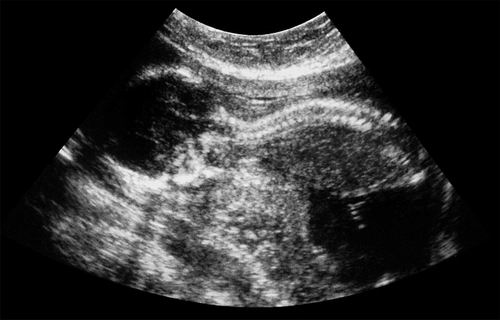

利用来自胎盘的干细胞,有望在子宫内治愈患有脊柱裂的胎儿。图片来源:Fraser/Science Photo Library